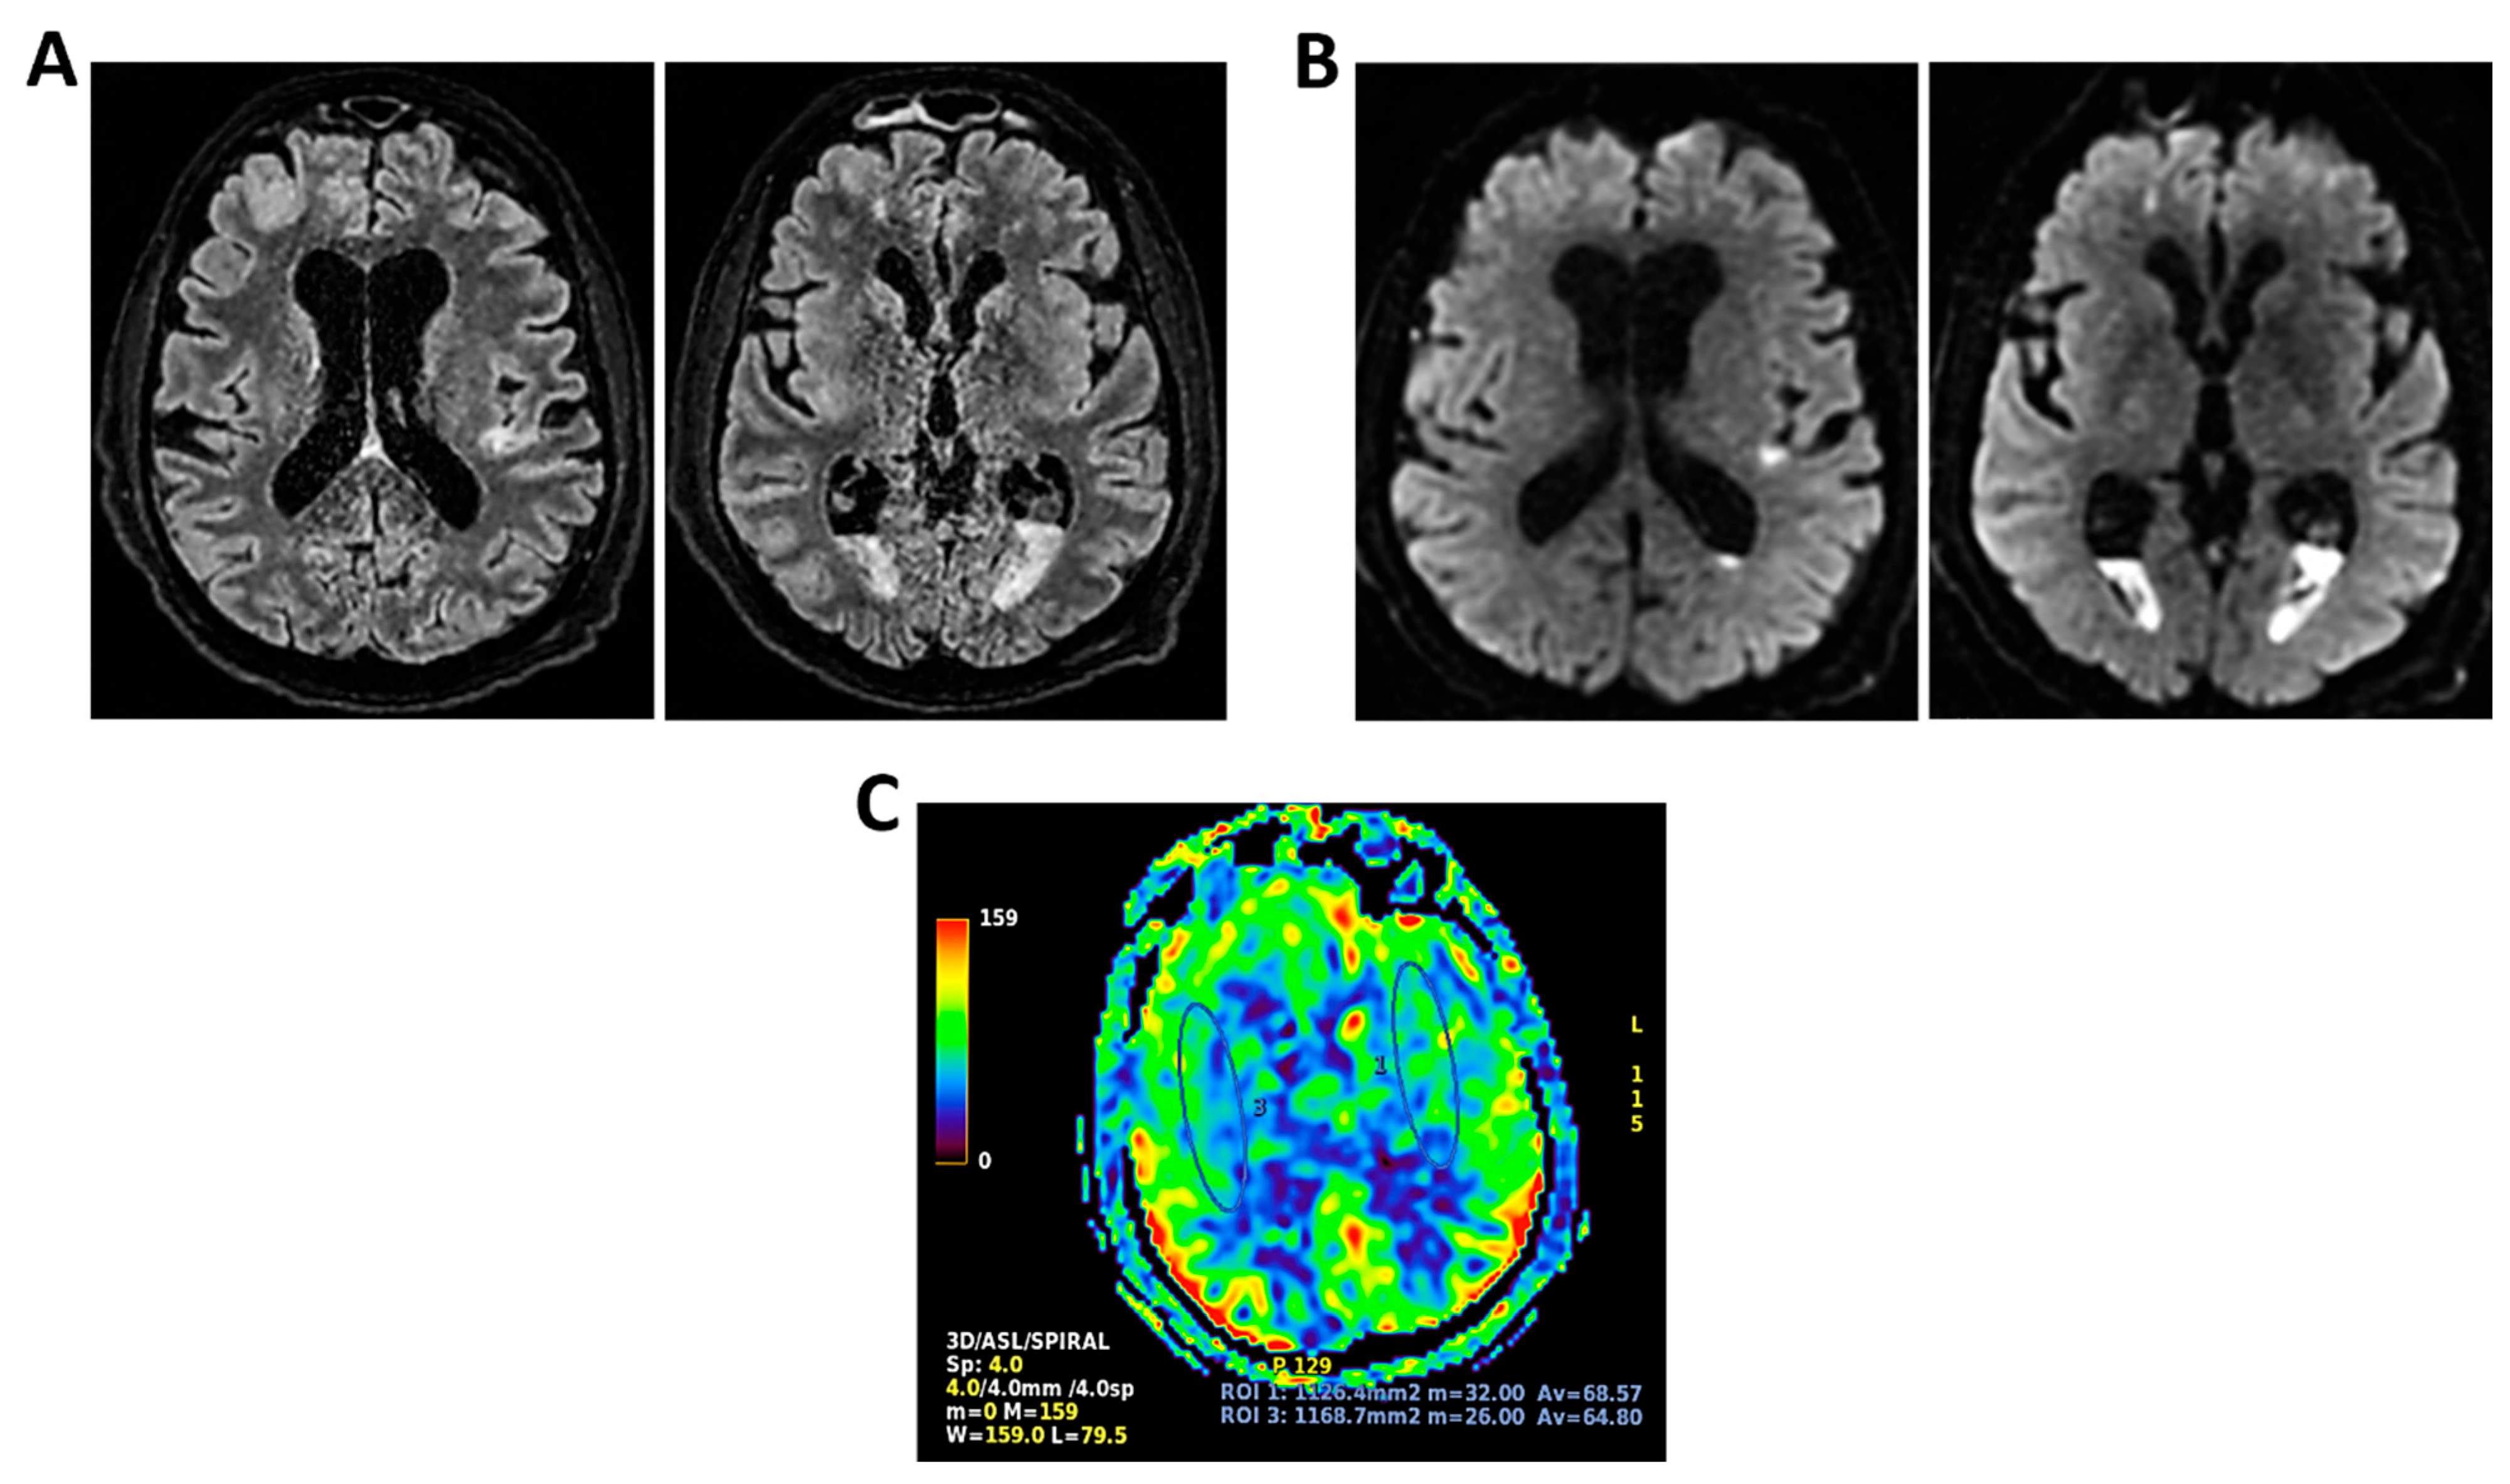

Figure 9.

MRI of patient 4 group 2. A 35-year-old HIV-positive man, diagnosed in 2018 with pneumocystosis (PCP) and non-compliant with Highly Active AntiRetroviral Therapy (Biktarvy), presented with bilateral otalgia, progressive hearing loss, left-sided hemiparesis, and impaired coordination. He was hospitalized and reinitiated Biktarvy and PCP prophylaxis with Bactrim. He received broad-spectrum antibiotics for bilateral otomastoiditis and ganciclovir for CMV viremia. Brain MRI revealed findings consistent with progressive multifocal leukoencephalopathy (PML). After discharge, worsening left hemiparesis and new-onset dysarthria led to readmission. A follow-up CT showed progression of subcortical white matter lesions. Lumbar puncture, urine, and plasma were all positive for JC virus. The patient was transferred to the ICU for further management. On day 2, TCCD showed PI of 1.50 on the right and 1.07 on the left, indicating mild asymmetry but no definitive signs of intracranial hypertension. (A) MRI exam shows large areas of altered signal intensity, without significant mass effect, hyperintense in 3D axial FLAIR sequence, (B) with peripherical diffusion restriction in axial DWI sequence, (C) without contrast enhancement in 3D axial T1 FSPGR, involving both cortical and deep regions of the frontal, temporal and parietal regions bilaterally, as well as right insular and thalamic regions. Additionally, the brainstem with left-sided predominance and the right middle cerebellar peduncle are involved. These alterations are consistent with PML. (D) MRI perfusion study documents minimal increase in CBF in the more cranial regions on the right. Blue circles indicate the ROI used for quantitative CBF analysis.